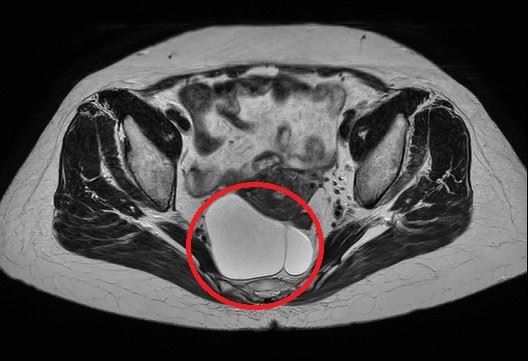

亞洲大學附屬醫院大腸直腸外科主治醫師傅軍毓表示,張女自述過去數十年來身體都沒有任何異狀,直到日前因車禍擦撞送醫,急診醫師安排腹部電腦斷層掃描才發現異狀,趕緊轉診到大腸直腸外科,再安排大腸鏡及核磁共振攝影,確認該腫瘤為「尾腸囊腫」(Tailgut cyst)約10公分大,已跟直腸壁緊貼,讓她看了驚呼「沒想到肚子裡有『拍咪ㄚ』。」。

傅軍毓醫師指出,「尾腸囊腫」屬於罕見先天性病灶,好發於中年女性,通常位在直腸與薦骨之間,多數患者沒有明顯或特殊症狀,一旦體積變大,可能壓迫周邊器官,雖然腫瘤多數以良性居多,但少數體積太大的腫瘤會出現惡性變化,因此多建議及早手術切除。